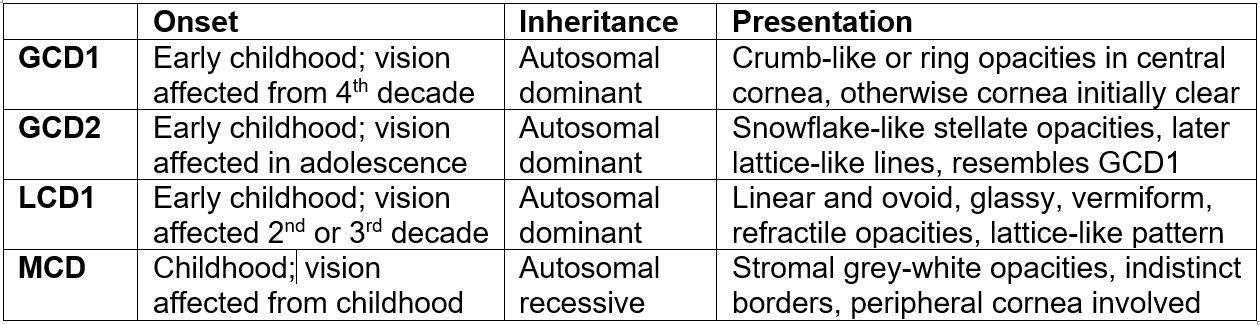

In its early stages, MCD can present similarly to granular dystrophy. However, it will often involve peripheral and deep layers of the stroma, which are typically spared with granular corneal dystrophies. An early stromal haze, thinning of the cornea and autosomal recessive family history supports this diagnosis (Fig 4). Table 1 highlights the differentiating features between these four granular dystrophies.

Table 1. Differentiating features between granular corneal dystrophy 1 and 2, lattice corneal dystrophy 1 and macular corneal dystrophy.